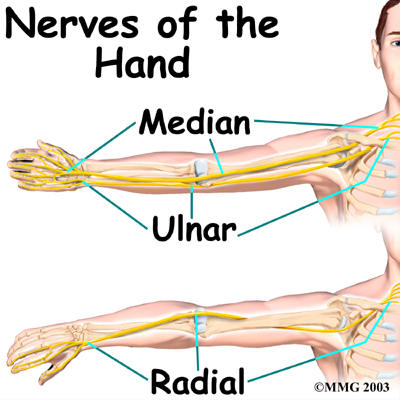

All of the nerves that travel to the hand cross the wrist. Three main nerves begin together at the shoulder: the radial nerve, the median nerve, and the ulnar nerve. These nerves carry signals from the brain to the muscles that move the arm, hand, fingers, and thumb. The nerves also carry signals back to the brain about sensations such as touch, pain, and temperature.

The

runs along the thumb-side edge of the forearm. It wraps around the end of the radius bone toward the back of the hand. It gives sensation to the back of the hand from the thumb to the third finger. It also goes to the back of the thumb and just beyond the main knuckle of the back surface of the ring and middle fingers.

The travels through a tunnel within the wrist called the carpal tunnel. The median nerve gives sensation to the palm sides of the thumb, index finger, long finger, and half of the ring finger. It also sends a nerve branch to control the thenar muscles of the thumb. The thenar muscles help move the thumb and let you touch the pad of the thumb to the tips each of each finger on the same hand, a motion called opposition.

The travels through a separate tunnel, called Guyon's canal. This tunnel is formed by two carpal bones (the pisiform and hamate), and the ligament that connects them.

The travels through a separate tunnel, called Guyon's canal. This tunnel is formed by two carpal bones (the pisiform and hamate), and the ligament that connects them.

After passing through the canal, the ulnar nerve branches out to supply feeling to the little finger and half the ring finger.

Branches of this nerve also supply the small muscles in the palm and the muscle that pulls the thumb toward the palm.